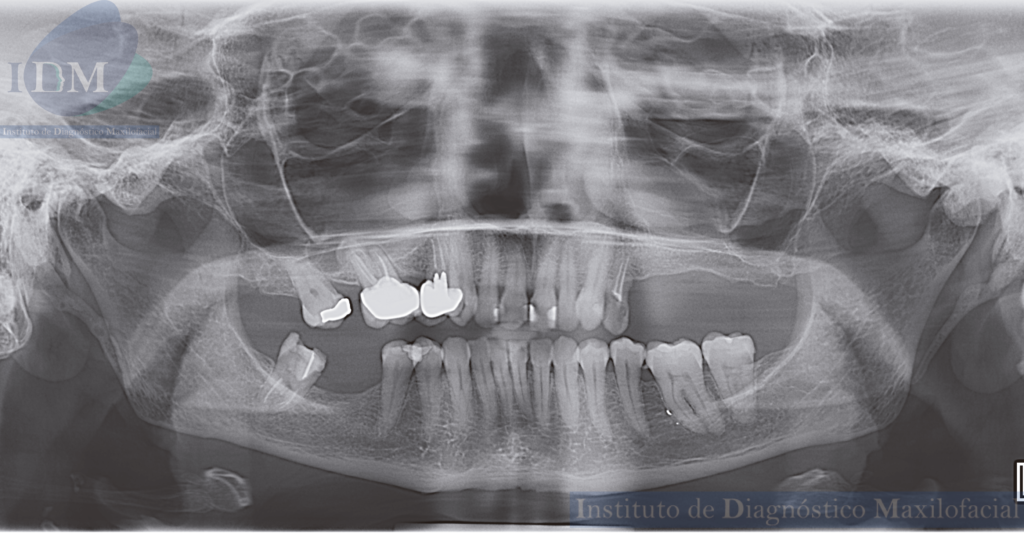

A la evaluación de la radiografía panorámica se aprecia mineralización del proceso estilohioideo bilateral, neumatización de ambos senos maxilares, además se visualiza presencia de placa cervical mineralizada, reabsorción ósea del proceso alveolar y múltiples piezas con presencia de obturación de conductos. La pieza 26 presenta procesos osteolíticos periapicales y corona protésica. Asimismo, se observó una imagen radiopaca de forma redondeada y limites definidos que se proyecta sobre el cóndilo mandibular del lado izquierdo, se realizó la ampliación del estudio con una tomografía cone beam.

Radiografia Panorámica

Radiográficamente, los osteomas periféricos generalmente se presentan como una lesión de engrosamiento óseo radiopaca bien circunscrita redonda u ovalada cuya base está unida con el hueso cortical subyacente, a menudo como una lesión pediculada pero también puede tener una base amplia (3)